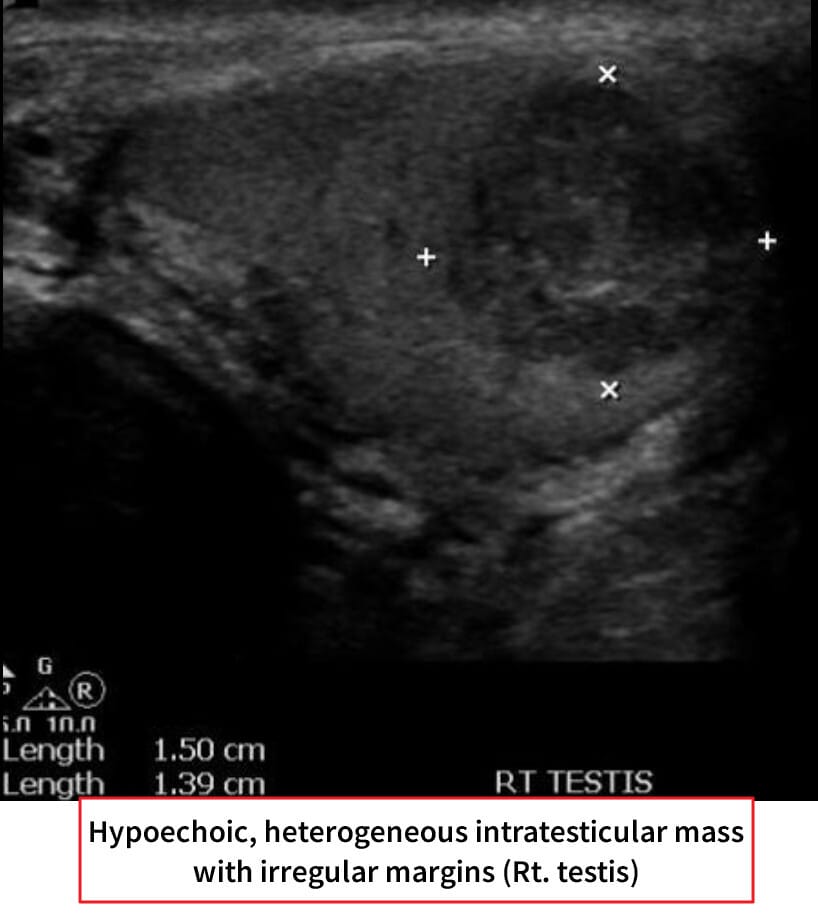

고환암 영상 소견

– 신체검사: 단단한 고환 종괴 촉지.

– 종양표지자: hCG 상승 가능, 그러나 AFP는 정상

– 영상검사: 고환 초음파에서 저에코성 종괴 확인.

– CT/MRI: 병기 설정 및 전이 평가.

– 확진: 고환 절제술(근치적 고환 절제술, radical orchiectomy)을 통한 조직학적 확인.